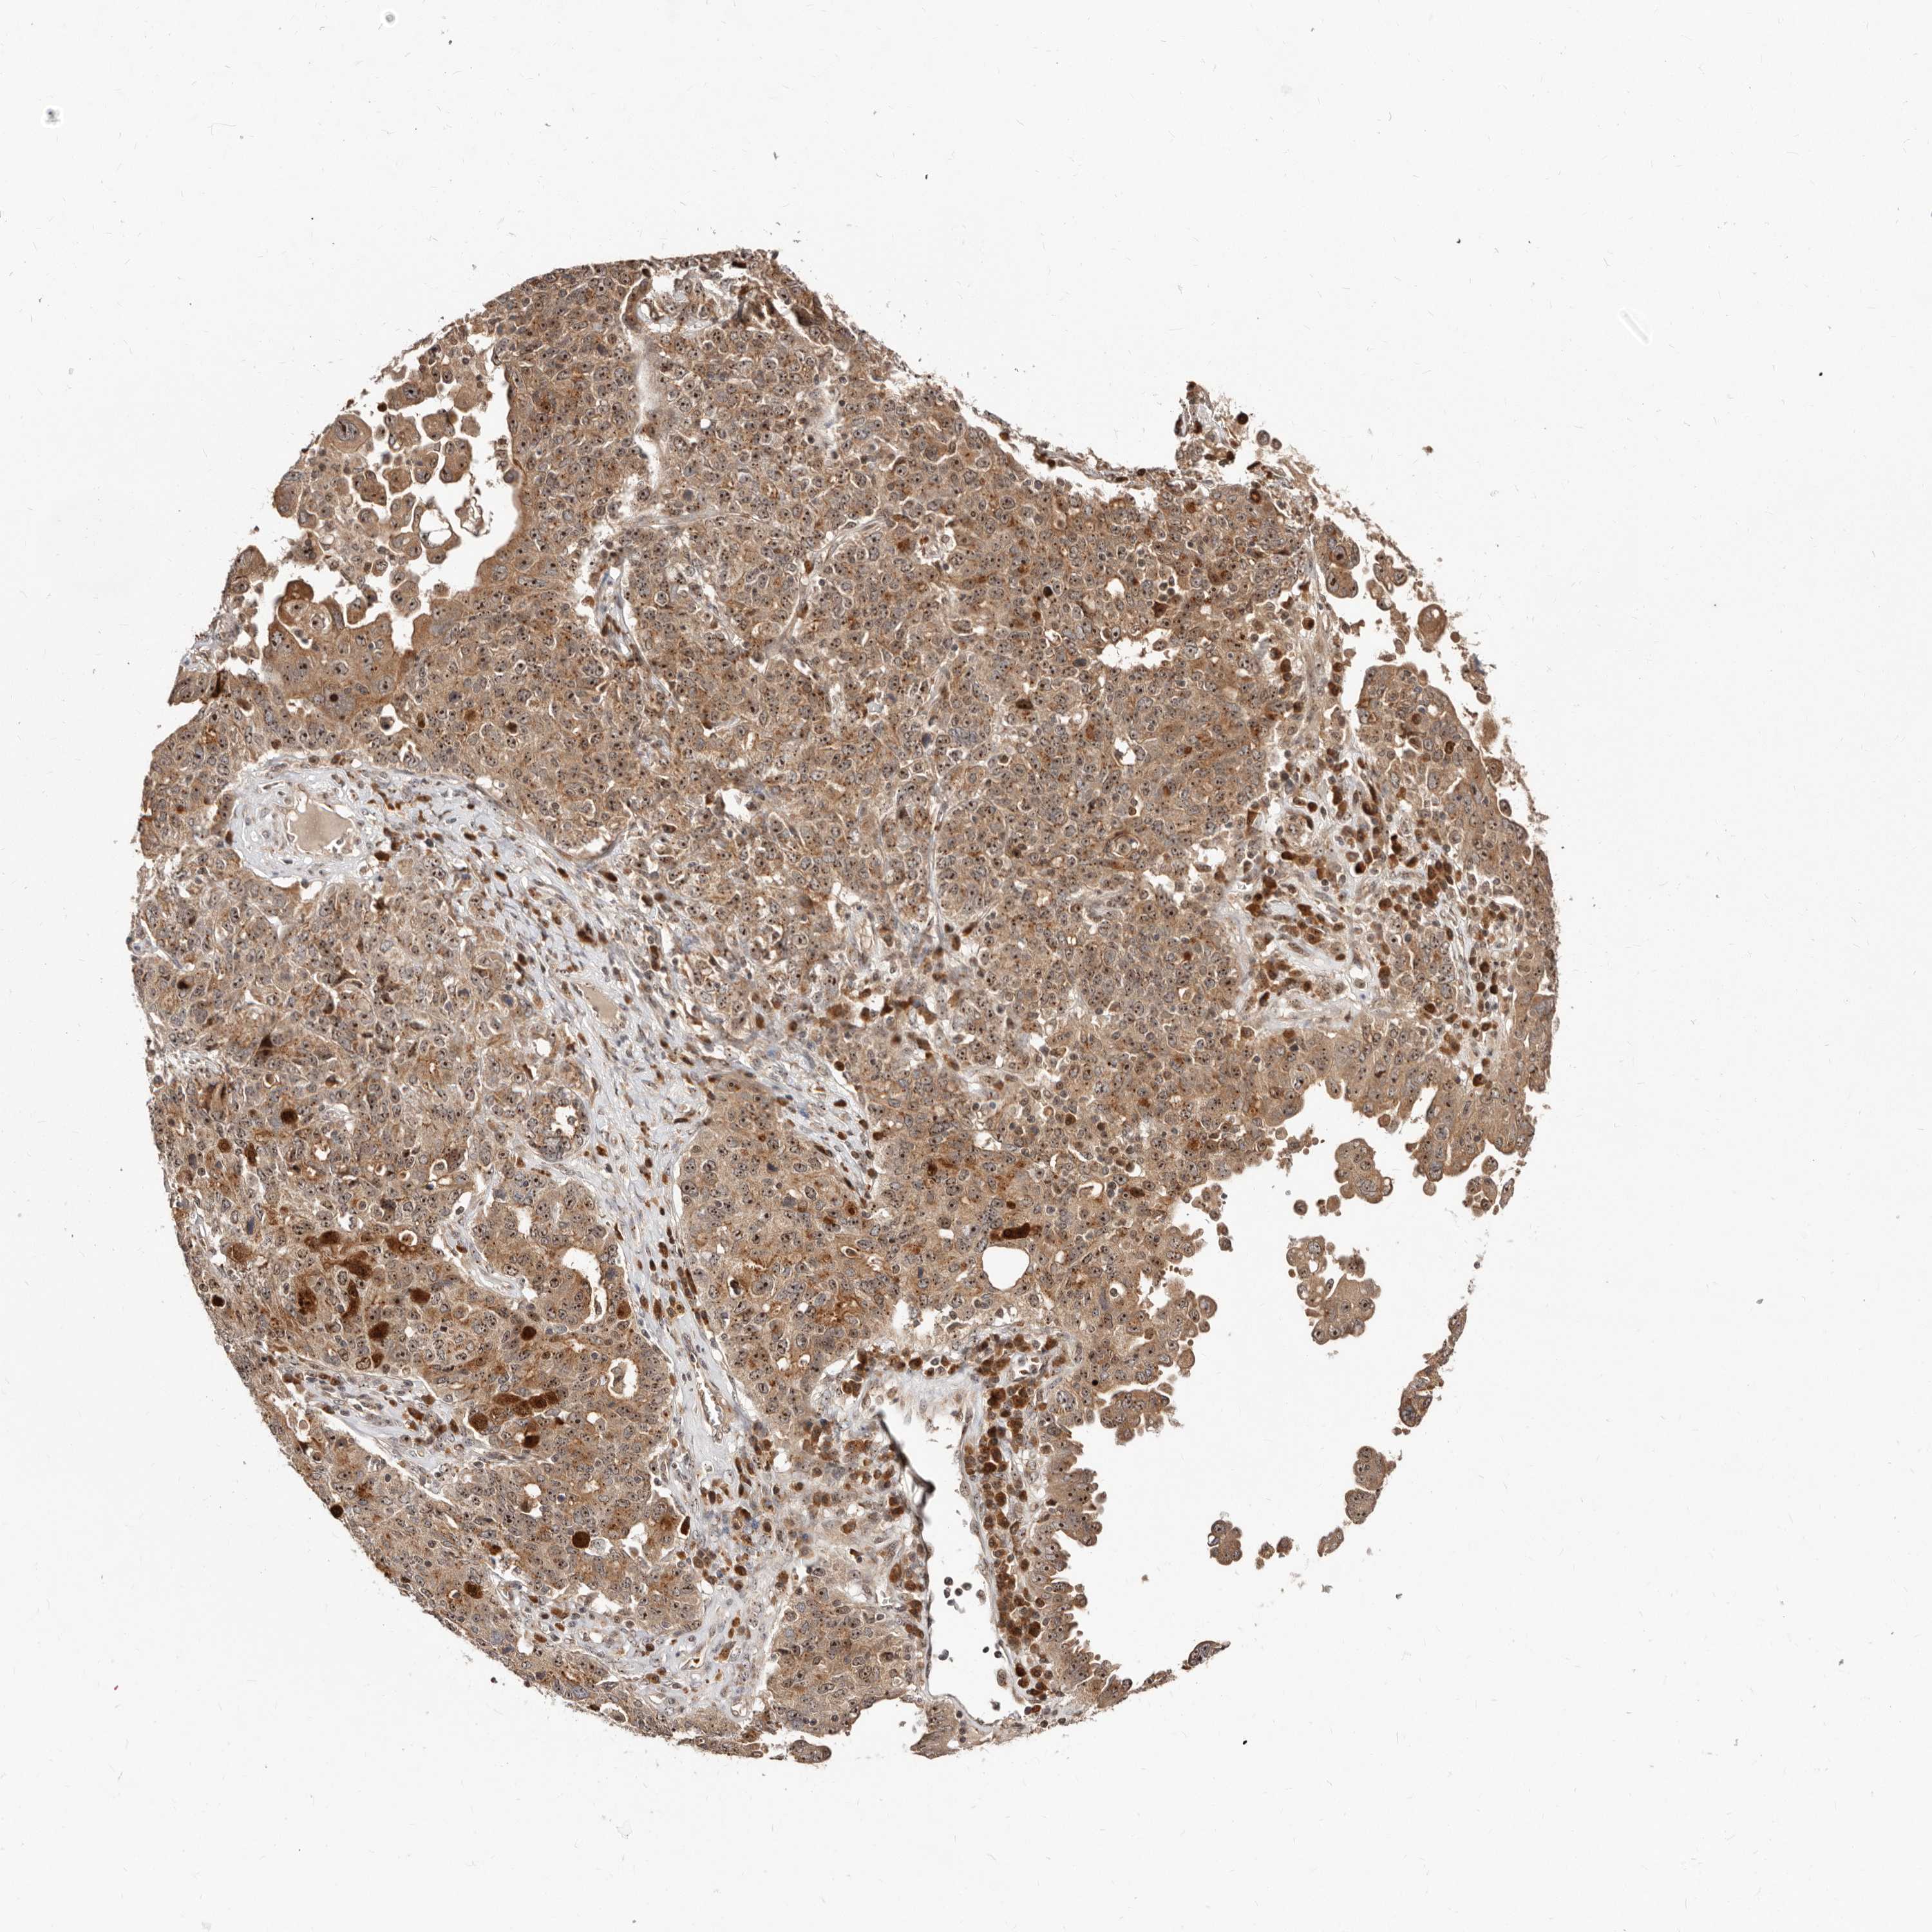

OVARIAN CANCER - Protein expressioni

A mouse-over function shows sample information and annotation data. Click on an image to view it in a full screen mode. Samples can be filtered based on level of antibody staining by selecting one or several of the following categories: high, medium, low and not detected. The assay and annotation is described here.

Note that samples used for immunohistochemistry by the Human Protein Atlas do not correspond to samples in the TCGA dataset.

Antibody stainingi

Antibody staining in the annotated cell types in the current human tissue is reported as not detected, low, medium, or high, based on conventional immunohistochemistry profiling in selected tissues. This score is based on the combination of the staining intensity and fraction of stained cells.

Each image is clickable and will lead to virtual microscopy that enables deeper exploration of all samples and also displays staining intensity scores, fraction scores and subcellular localization as well as patient and tissue information for each sample.

Antibody HPA029165

Antibody HPA029167

Antibody CAB028574

Cystadenocarcinoma, mucinous, NOS